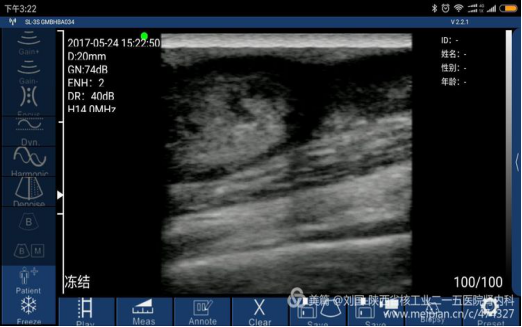

Cephalic vein condition checked by Sonostar’s wireless ultrasound, and displayed by my mobile phone-Mi max